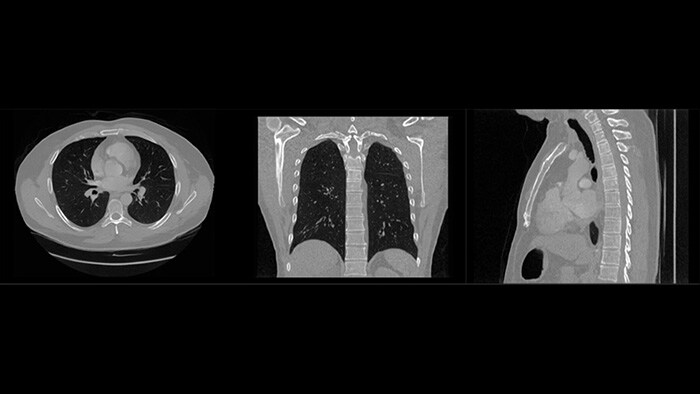

As part of a larger innovation partnership, Dr. Akre and his team joined forces with Philips to create a web-based application for structured information sharing. “Clinicians from different disciplines have been involved from the start, because we wanted to make sure that the application is tailored to their needs,” says Dr. Akre. “Philips has translated those needs into an easy-to-use application. We now have a well-tested prototype that we are using for a clinical trial.” Clinicians can enter both text and images into the application. All patient information is stored in a secure and structured database. Based on that information, the application creates a dashboard which shows the right information to the right clinician at the right time. Dr. Akre: “For example, when I’m meeting with a patient, I will immediately get an overview of any side effects the patient might be experiencing from treatment. This means I don’t have to ask the patient unnecessary questions, but instead, I can focus on tailoring the follow-up treatment to the needs of the patient.” “We will also benefit from the application during our multidisciplinary meetings,” Dr. Akre continues. “When we’re discussing patients together, it saves time and helps with decision-making if we all have the same structured overview of patient information at our fingertips.”